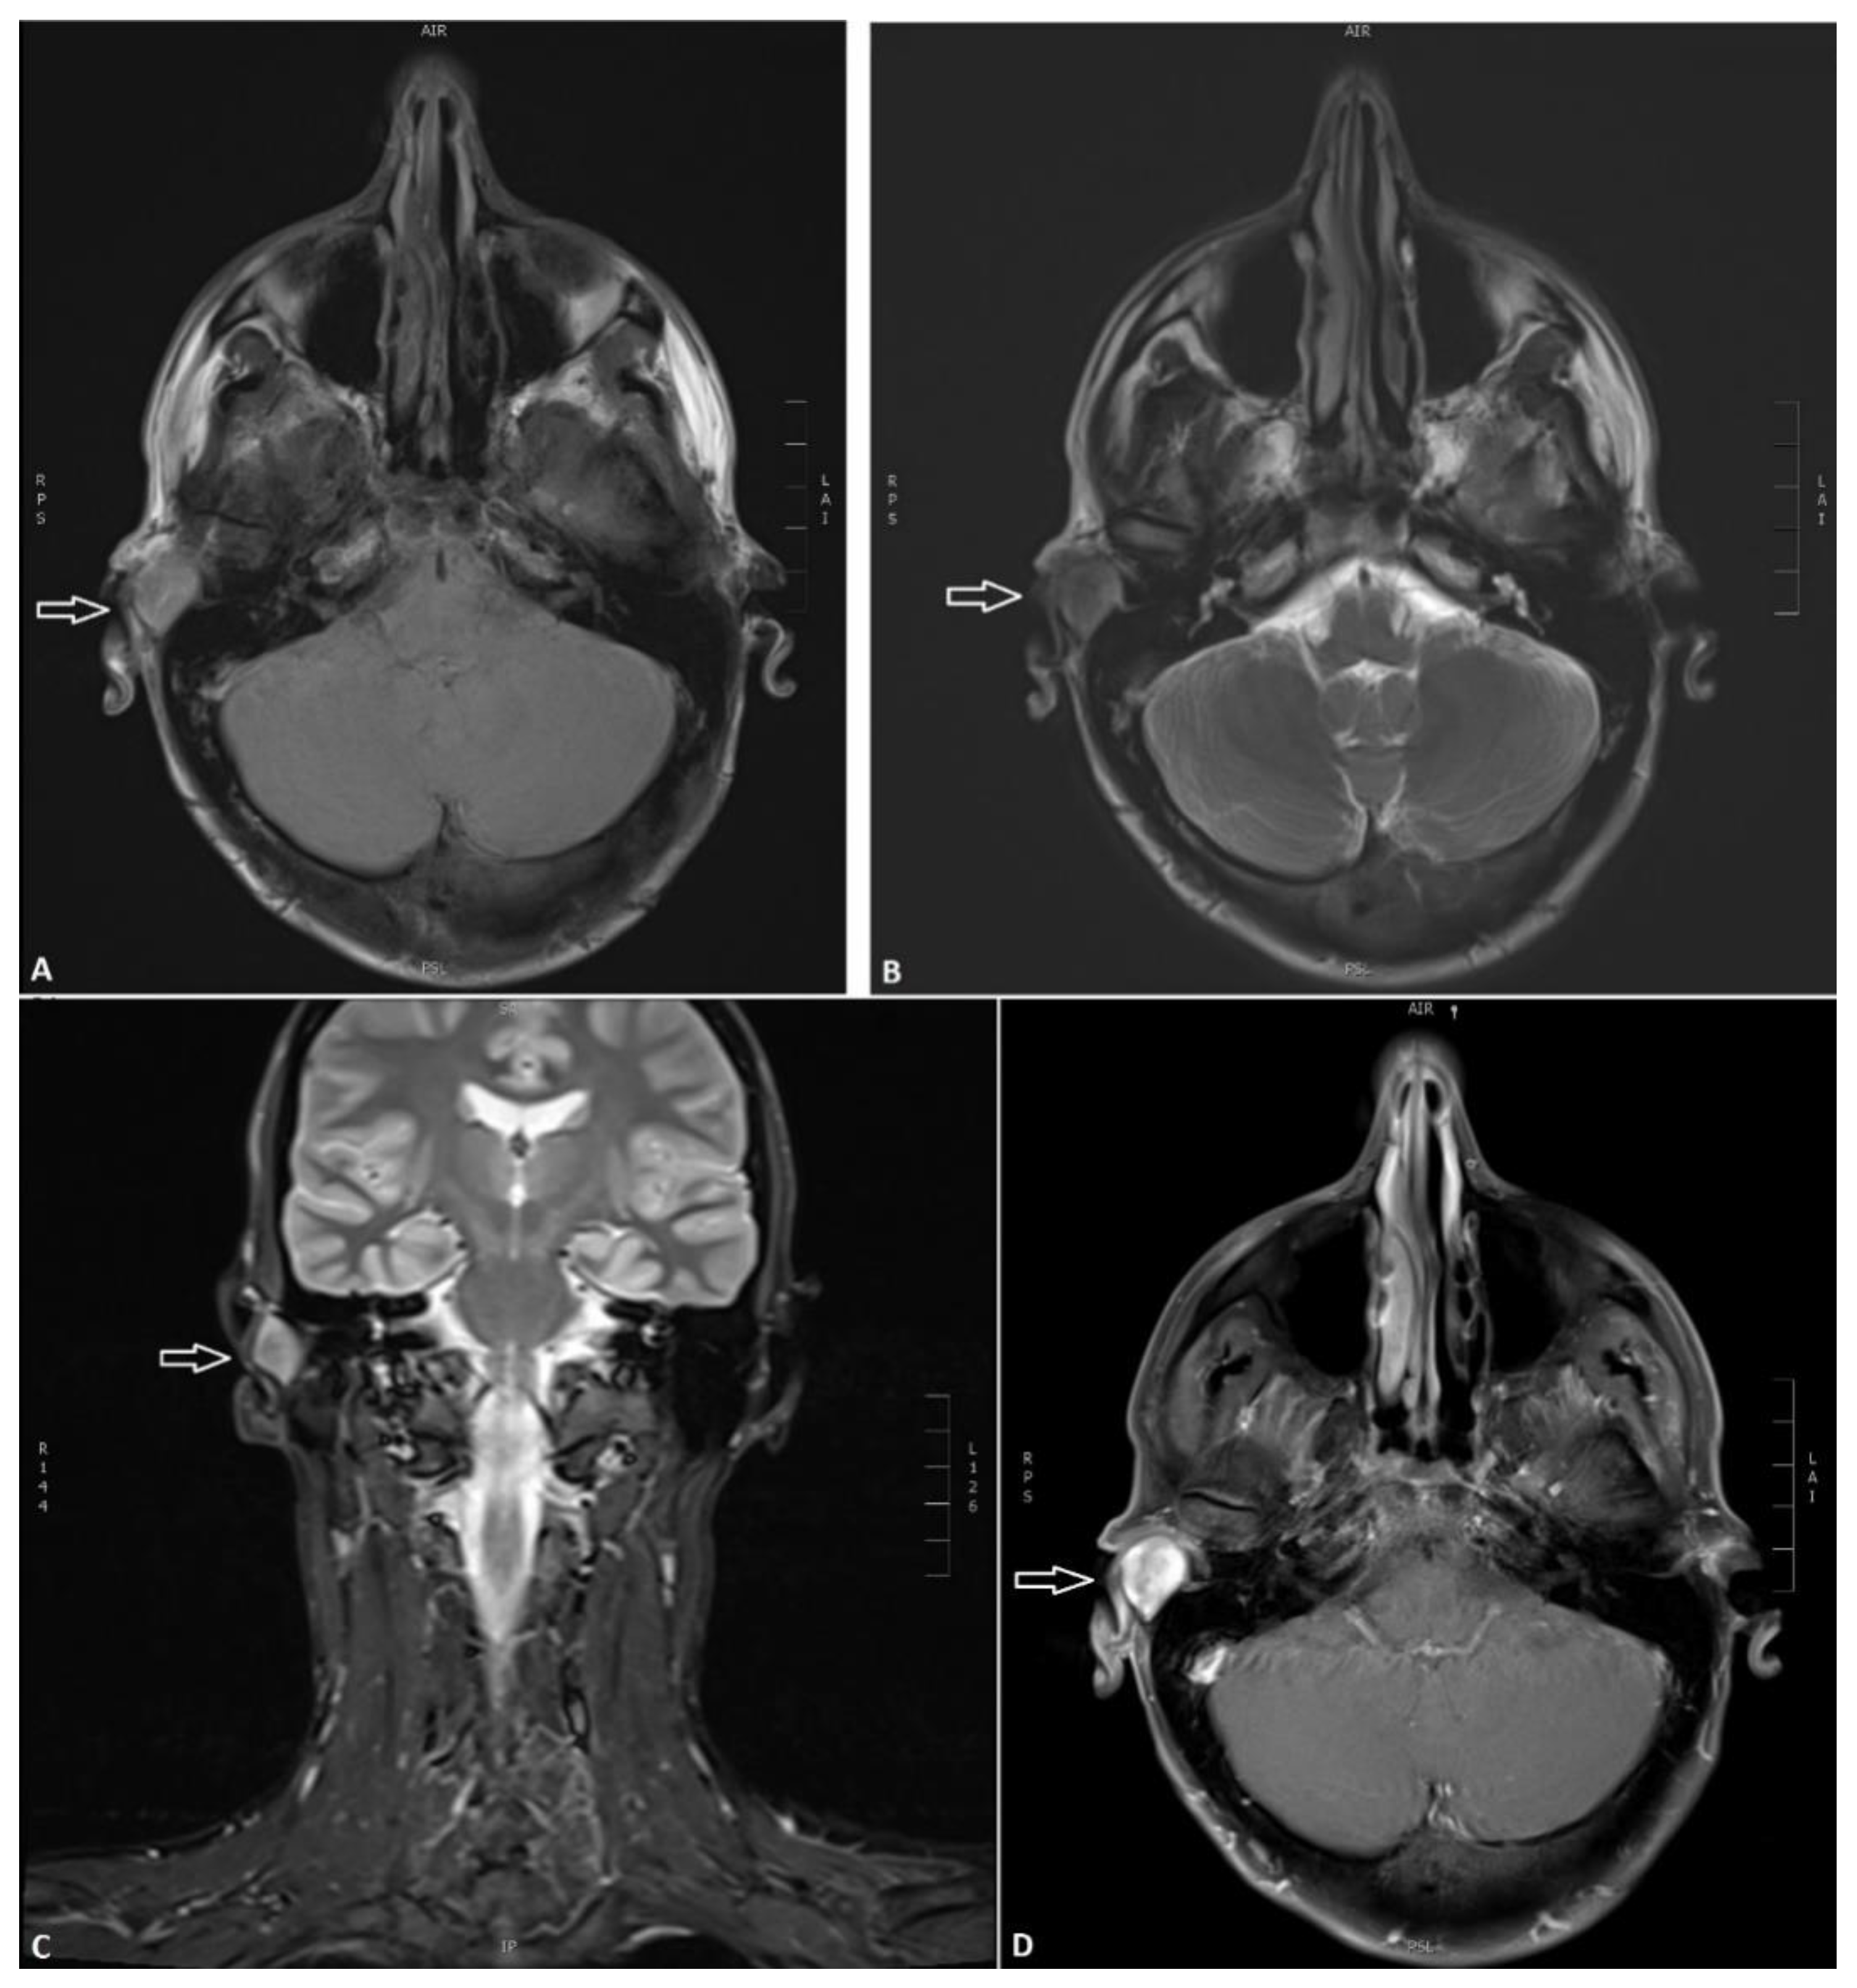

2. Case Report